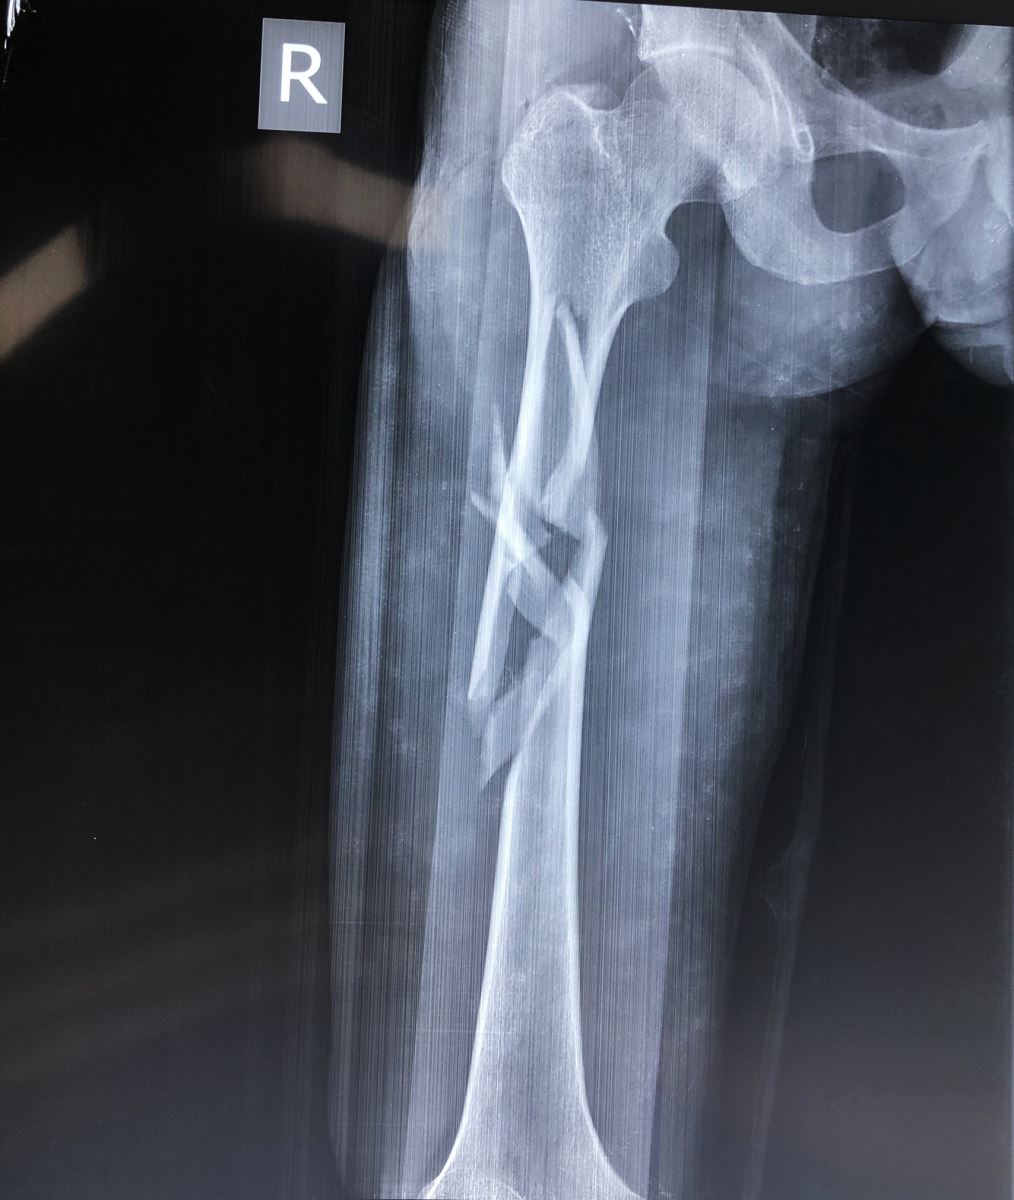

1.2. Đường gãy

Gồm có gãy ngang, gãy chéo, gãy xoắn, gãy 2 ổ hoặc gãy vụn.

- Đường gãy ngang: Thường do gập góc, dạng gãy này sau khi nắn tốt thì thường vững chắc hơn các dạng gãy khác.

- Đường gãy chéo, xoắn: Thường do gập góc kèm theo vặn xoắn cơ thể. Dạng gãy này không vững chắc sau khi nắn

1.3. Sự di lệch

Tuỳ theo vị trí gãy và có các hình thái di lệch khác nhau. Các di lệch thường gặp là gập góc, lệch sang bên, chồng lên nhau, xoay ngoài của đoạn gãy xa.

3. CHẨN ĐOÁN HÌNH ẢNH (X-QUANG)

Mặc dù chẩn đoán bằng X quang là cần thiết, nhưng cần khám kỹ lâm sàng để tránh bỏ sót thương tổn. Một số trường hợp bỏ sót trật khớp háng trong gãy thân xương đùi vì chỉ chụp giới hạn ổ gãy. Do vậy để có một phim X quang tốt cần chú ý:

- Chụp lấy được 2 khớp của đầu xương gãy ít nhất hai bình diện thẳng và nghiêng.

- Chụp xương bên lành để so sánh nếu thấy cần thiết.